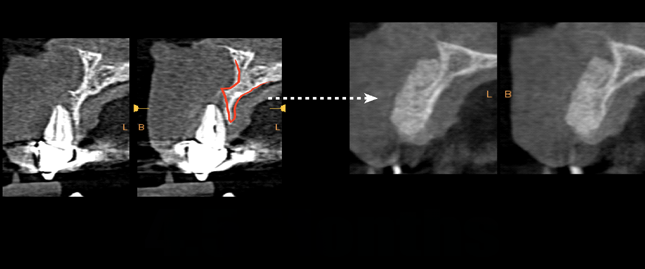

Fig 10. Preoperative versus postoperative CBCT. Cross-sectional comparison between the preoperative and postoperative conditions at

4.5 months postoperatively is shown. Note the large amount of graft volume obtained creating a proper site for implant placement.